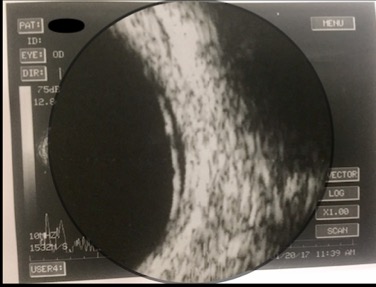

- Ultrasonography (B-Scan): B-mode ultrasound is useful for documenting and monitoring serous retinal detachment, which can occur in hypertensive retinopathy. It provides valuable insights into the extent and progression of retinal detachment.

- Ultrasonography